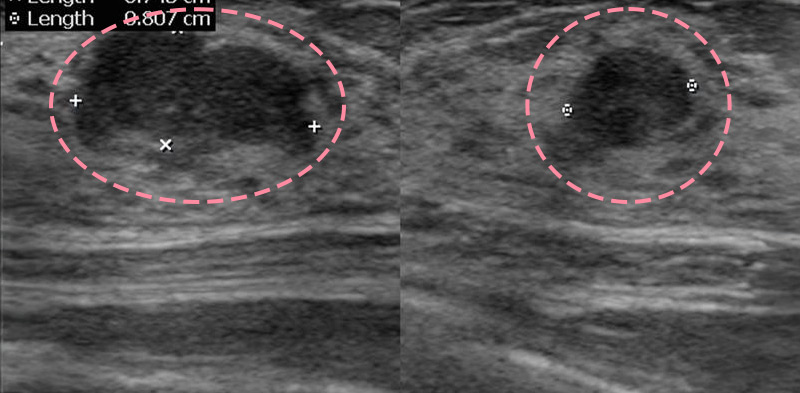

맘모톰시술 후 병리조직검사에서 상피내암(조기유방암)으로 진단되어 대학병원으로 연계해 드린 환자분의 사례입니다. 암을 초기 단계에 찾음으로써 항암치료 없이 간단한 수술을 통해 치료가 가능하였습니다.

유방 양성 종양은 한 개만 나타나는 것이 아니라 동시다발적으로 생겨나기도 합니다.

여러 개의 양성 종양 제거는 정상적인 유방 조직을 온전히 보전할 수 있도록 섬세한 시술이 필요합니다.

한송이 원장은 다발성 종양 제거에 대한 풍부한 경험을 토대로, 무리 없이 맘모톰 조직검사 및 제거를 진행했습니다.

맘모톰시술 6개월 후 유방초음파 검사 시행 결과 종양이 깨끗하게 제거됨을 확인했으며, 약간의 반흔 조직이 남았으나 시간이 지나면서 대부분 사라지기 때문에 좋은 예후가 기대되었습니다.